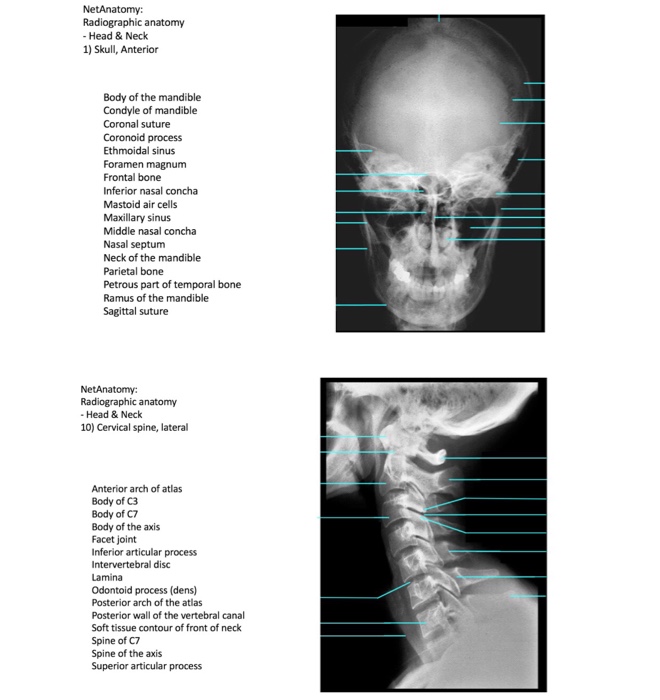

Solved Netanatomy Radiographic Anatomy Head Neck 1 Sku